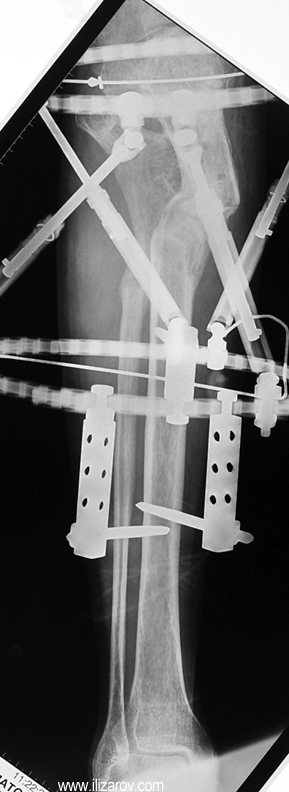

The bifocal compression technique described by Ilizarov, which consists of acute shortening and gradual distraction, allows acute shortening of 4-5 centimeters in tibial defects; defects exceeding this amount can be further shortened gradually by 3 millimeters per day. The same principle is also applicable to the femur, allowing an acute shortening of 8 centimeters. This method facilitates reconstruction of bony continuity and primary or delayed primary closure of soft tissue defects, which would would avoid the requirement for free flaps. A second corticotomy in the metaphyseal region may be used to restore the original length of the shortened bone and to increase it’s vascularity. Intramedullary osteosynthesis of intra-/periarticular fractures is a borderline indication. Open reduction and internal fixation of these fractures hazards the blood supply to (small) bone fragments by extensive dissection, and nonunion or infection is (iatrogenically) invited. In contrary, percutaneous or indirect reduction by limited dissection, small wire and percutaneous cannulated screw osteosynthesis, augmented by external fixation, provides a stable construction to allow early mobilization, range of motion exercises and sometimes partial weight bearing.

My preference in these cases is to use circular external fixators, which are modular, permit fixation of small reduction wires to the frame, and enable postoperative angular adjustments. Recently, combined techniques using external fixators and intramedullary rods have been introduced. The advantage of this method is to decrease the external fixation time by about 50% and to enhance the patient’s comfort.

Case 3